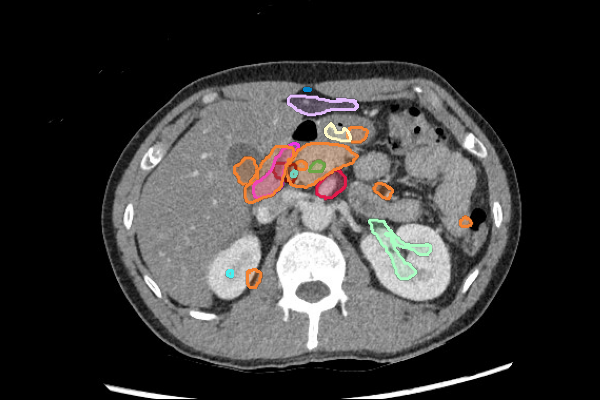

- Liver lesions can be subtle. Use a "Liver" window to increase sensitivity.

- Masses in the mesentery/peritoneum are often overlooked. Take advantage of multiplanar imaging and look in characteristic locations for peritoneal lesions.

- Kidney masses are also overlooked. Look carefully at the collecting system and for renal contour abnormalities.

Mass or Adenopathy

Infection or Inflammation

Legend

Slice 1

Slice 2

Slice 3

Slice 4

Slice 5

Slice 6

Slice 7

Slice 8

Slice 9

Slice 10

Slice 11

Slice 12